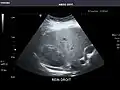

Kidneys: Right and left kidneys measure 11.5 cm and 12 cm in length respectively. No hydronephrosis. Small left lower pole kidney cyst.

Left kidney -